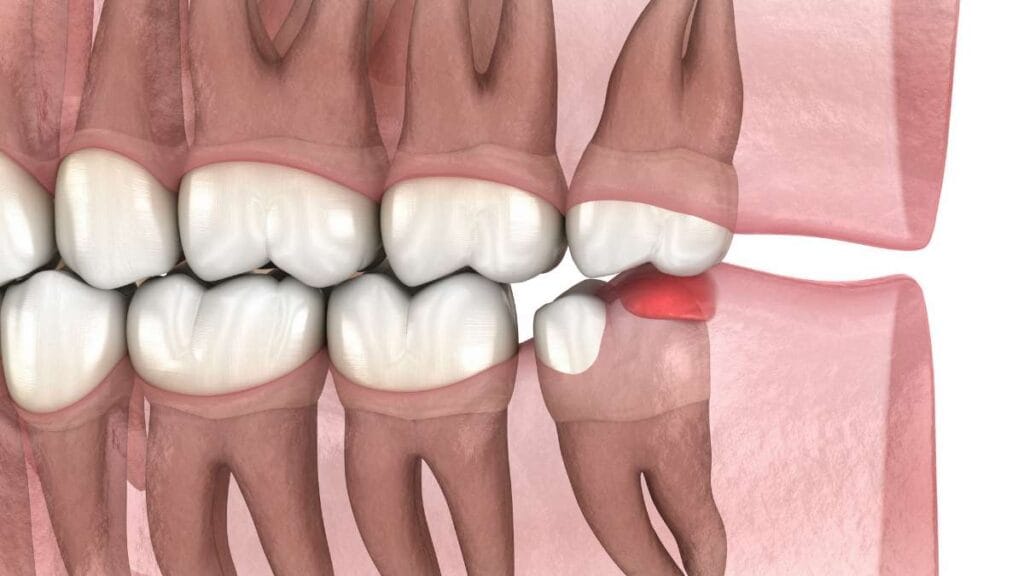

Çene kemiğinde yer bulamayan 20’lik dişlerin çevre dokularda oluşturabileceği baskı ve hassasiyetin oluşum mekanizması.

Yer darlığı ve gömülü kalma: Diş sürecek alan bulamadığında kemik içinde ya da diş eti altında takılı kalabilir. Bu durum, komşu dişe baskı yaparak ağrıya ve zamanla o dişte hasara yol açabilir. Özellikle yatay konumlanmış dişlerde bu baskı daha belirgin olabilir.

Alt çene gömülü 20’lik dişlerin çevre dokularda ve komşu dişte oluşturabileceği baskı ve enflamasyon (iltihap) durumu.